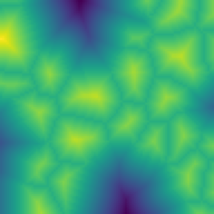

Specular microscopy assessment of the human corneal endothelium (CE) in Fuchs' dystrophy is challenging due to the presence of dark image regions called guttae. This paper proposes a UNet-based segmentation approach that requires minimal post-processing and achieves reliable CE morphometric assessment and guttae identification across all degrees of Fuchs' dystrophy. We cast the segmentation problem as a regression task of the cell and gutta signed distance maps instead of a pixel-level classification task as typically done with UNets. Compared to the conventional UNet classification approach, the distance-map regression approach converges faster in clinically relevant parameters. It also produces morphometric parameters that agree with the manually-segmented ground-truth data, namely the average cell density difference of -41.9 cells/mm2 (95% confidence interval (CI) [-306.2, 222.5]) and the average difference of mean cell area of 14.8 um2 (95% CI [-41.9, 71.5]). These results suggest a promising alternative for CE assessment.